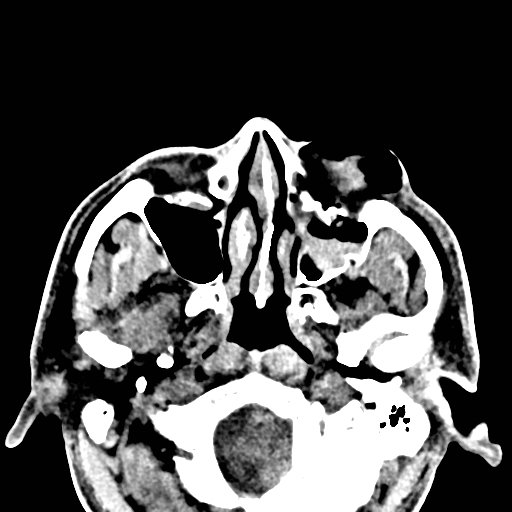

Physical exam showed marked left palpebral subcutaneous crepitus, as well as bulbar and palpebral conjunctival bulging. Visual acuity was normal with intact extraocular movements, and normal pupillary exam. Computed tomography (CT) imaging of the face was obtained and revealed multiple displaced fractures involving the left orbital floor and zygomatic arch associated with moderate periorbital and postseptal extraconal gas, resulting in orbital proptosis.